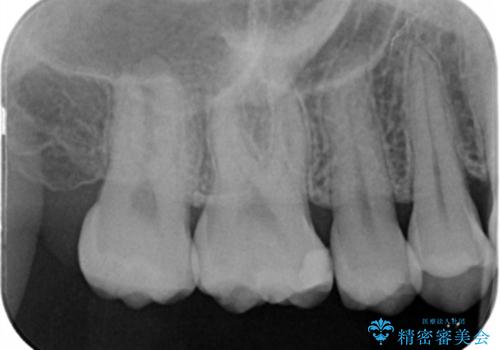

- 右上6番の保険材料で詰められた部分をセラミックにやり変え希望の患者様です。

切削量などを考慮し、セラミックインレーでの治療を選択しました。

う蝕が深くまで進行していたので、全て除去した上でCR裏層を行い形成、印象を行っています。